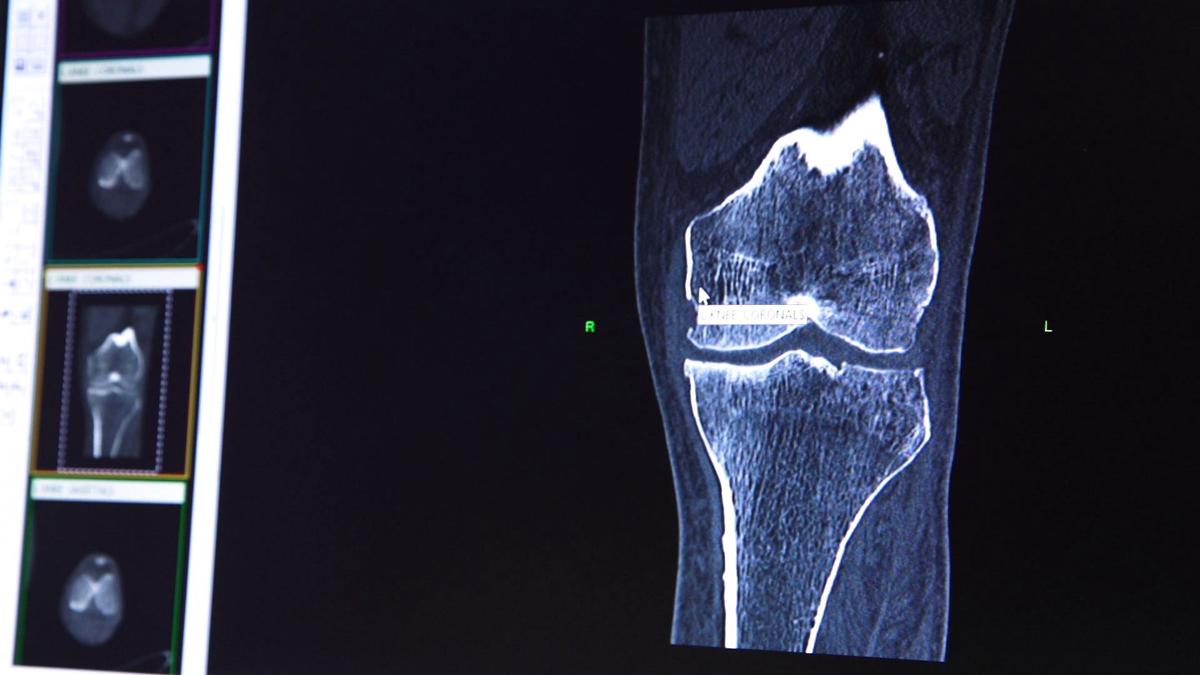

Conformis 3d Knee Replacement

Conformis Patient Specific Custom Total Knee Replacement

Custom Implants Houston Tx Conformis Knee Implant Cypress Tx

Lexington Surgeon Customizes Knee Replacements With 3d Technology

Conformis Knee Replacement Florida Orthopaedic Institute

Conformis Knee Baton Rouge La Knee Resurfacing South Louisiana